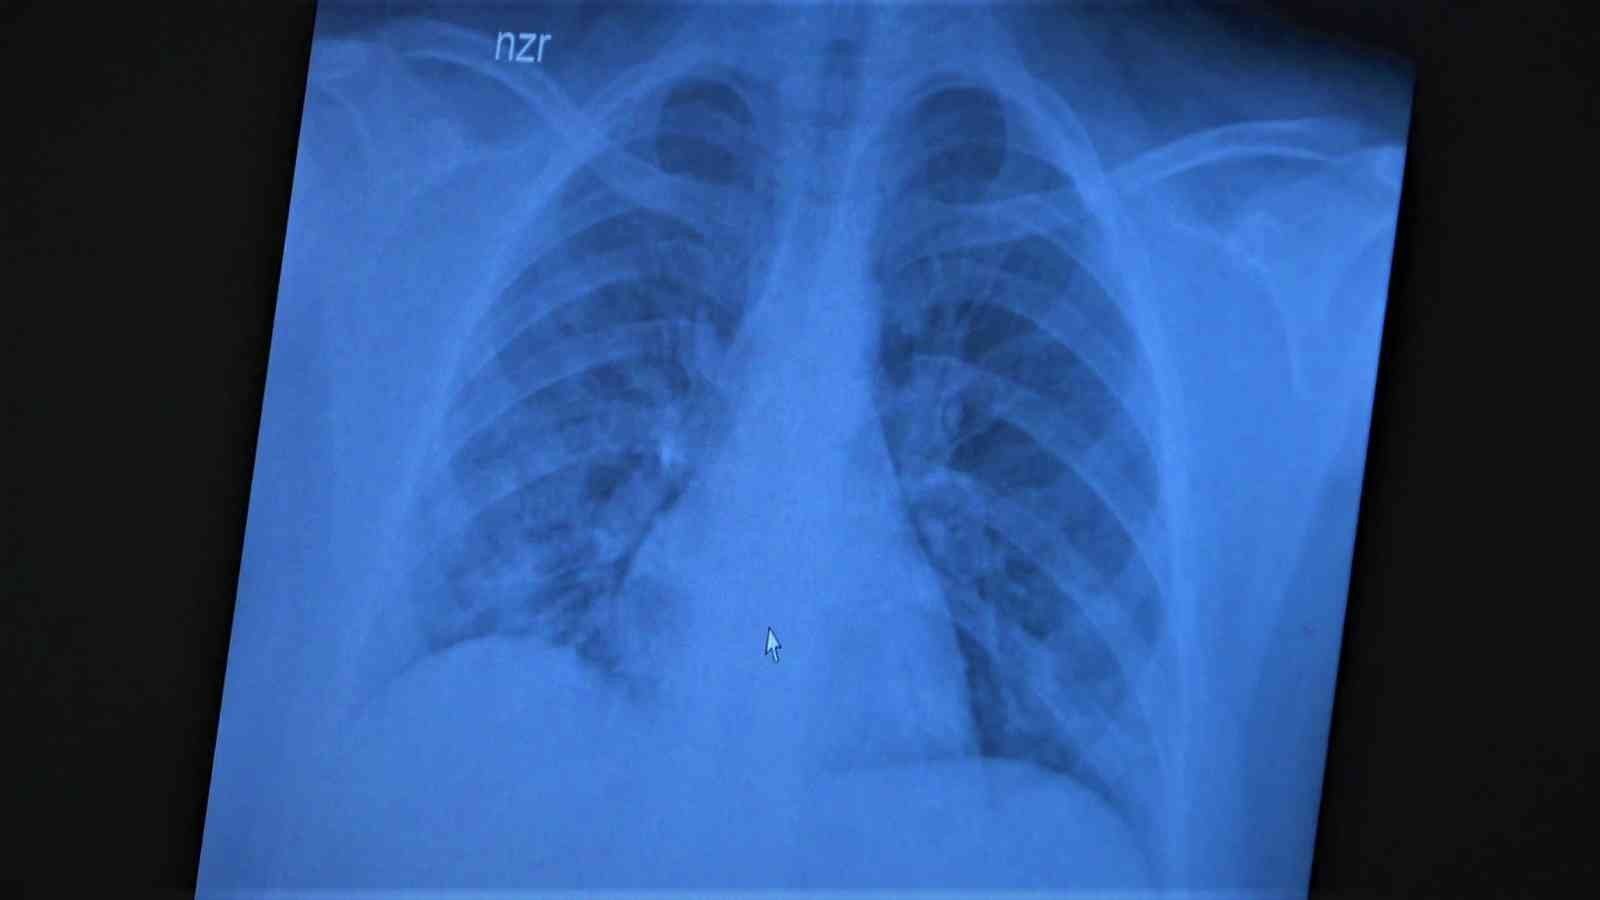

Korona virüsün mutasyona uğramış hali artık aşısız çocuklara ciddi zararlar vermeye başladığına dikkat çeken Göğüs Hastalıkları Uzm. Prof. Dr. Özkaya, 11 ve 14 yaşlarındaki koronaya yakalanmış ve ciddi akciğer tutulumlarıyla tedavi gören çocukların akciğer tomografilerini gözler önüne serdi.

Çocukların akciğer tomografilerini inceleyen Özkaya, "11 yaşında kovid pozitif bir öğrencimiz, yüksek ateş ve nefes darlığı ile bize geldi. Ciddi akciğer tutulumu var. Geçen yıl 'bu çocuklar hastalıktan etkilenmiyor' diyorduk. Bu çocukta görüyorsunuz buzlu camlar ve konsolidasyon alanlarla seyrediyor. Geçen yıl bu şekilde çok çocuk görmüyorduk. Önümüzdeki aylarda bu şekilde devam ederse çocuklarımızı kaybetmeye bile başlayabiliriz. 14 yaşında pozitif olan bir diğer çocuğumuz ise aşı randevusu almış ama aşısını olmadan ateş ve öksürükle başvurdu. Halen şanslıyız. Çocuklar tedaviye çok hızlı yanıt veriyor. Çekilen tomografisinde ise bilaterel yaygın tutulumları vardı. Bu ise 24 yaşında genç hastanın akciğer tomografisi. Bu kişide yaygın akciğer tutulumları görüldü. Bunu da tedavi ettik. Önümüzdeki aylarda ne getirecek ne götürecek beraber göreceğiz. Özellikle havaların soğumasıyla kapalı ortamlarda geçirilen zamanın ve kalabalıkların etkisiyle vaka sayılarının önümüzdeki günlerde artacağını biliyoruz. Şu an hastalık gerçekten 30-40 yaş altı gençlerde görülmeye başladı. Poliklinik şartlarında olanların büyük bir kısmı 30 yaş altı hastalar. Servislerde yatanlarda orta yaş ve altı nüfus. Yoğun bakımda yatanların büyük bir kısmı ise aşısız erişkin insanlardan oluşuyor" diye konuştu.